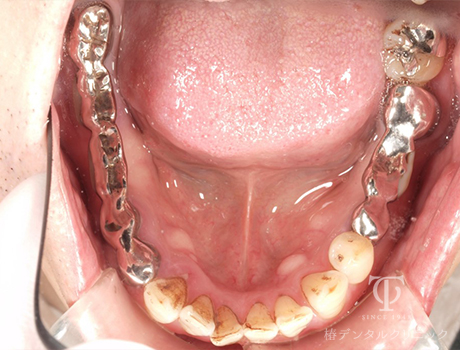

術前

-